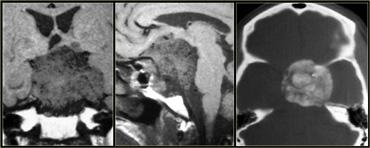

Hình bên trái là một khối u nằm ở vùng tuyến tùng.

Dựa trên những hình ảnh này, chẩn đoán phân biệt bao gồm:

- U màng não (Meningioma)

- U tế bào tuyến tùng (Pineocytoma)

- U tế bào mầm (Germ Cell Tumor)

Đây thực ra là một trường hợp u màng não (meningioma).

Hình bên trái là hình ảnh điển hình của u bì (dermoid) vùng tuyến tùng bị vỡ.

Hình bên trái là hình ảnh của bệnh nhân nam 12 tuổi với biểu hiện liệt nhìn lên.

Có một khối u nằm ở vùng tuyến tùng.

Khối u chứa vôi hóa.

Có ngấm thuốc đồng nhất, đây là đặc điểm thường gặp của khối u vùng tuyến tùng (đã đề cập ở trên).

Dựa trên tuổi bệnh nhân, vị trí và đặc điểm khối u, chẩn đoán có khả năng nhất là u tế bào mầm (germinoma).